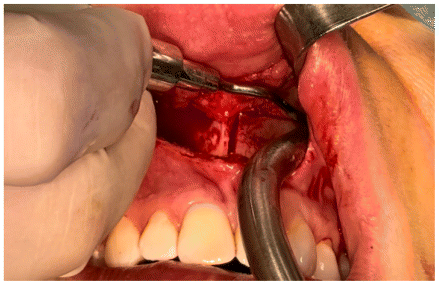

The osteotomy was composed of both horizontal and vertical segments (Figures 6,7,8). The horizontal segment was executed at the level of the piriform aperture, extending to the posterior maxilla and zygomatic buttress, with incisions made on the anterior and medial walls of the maxillary sinuses, while maintaining the cut just above the dental roots and following a slightly oblique inclination. This procedure was replicated on both the right and left sides. Subsequently, a vertical osteotomy was performed along the midline between the central incisors, corresponding to the median palatal suture, extending to the terminus of the bony palate at the midline. All osteotomies were carried out utilizing piezoelectric technology, with refinements made using a chisel by flexing (Figure 9).

Subsequent to the osteotomies, controlled activation of the MARPE device was executed to evaluate the resistance of the midline bone. The procedure was concluded with achieving hemostasis, irrigating with sterile saline solution, and suturing. (Figure 10)